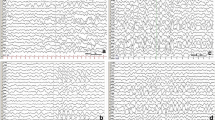

After admission, the patient was fed with formula milk and treated with phenobarbital followed by intravenous maintenance doses. Epileptic electrical activity was observed on a continuous normal voltage background pattern with immature sleep-wake cycling during amplitude integrated electroencephalogram(aEEG) monitoring (Fig. 1). Lab tests revealed normal serum glucose and high lactic acid levels (5.5 mmol/l), while ammonia levels were not tested. Blood gas tests revealed respiratory alkalosis, with PH 7.54, PCO2 of 20 mmHg, HCO3 of 21.5 mmHg, and BE of − 3.29 mmol/L. Electrolytes, liver enzymes, and creatine phosphokinase levels were normal. The newborn had no fever, vomiting, drowsiness or irritability. The physical examination indicated good responsiveness, a flat anterior fontanelle, normal muscle tone and no signs of nervous system dysfunction. Additionally, the complete blood count was normal: the leukocyte count was 12.3 × 109/L with neutrophils prevailed, hemoglobin levels were 130 g/L, and platelet count was 371 × 109/L. In addition, C-reactive protein was < 1.0 mg/L. There was no basis for intracranial infection; thus, we did not conduct a lumbar puncture. There were no obvious abnormal signs found in the head CT. Echocardiogram showed an atrial septal defect without cardiomyopathy.

The aEEG of the 2-day-old patient. The aEEG showed a continuous normal voltage background pattern with immature sleep-wake cycling. Epileptic electrical activities in regular electroencephalogram at 10 s (the time corresponding with gray line in aEEG tracing) are displayed in the lower part of the figure. Epileptic electrical activities were mainly seen in right frontal temporal region

On day 3 in the NICU, without additional anticonvulsants were administered, the convulsion frequency decreased. By day 5, no further clinical seizures were noted, and a repeated aEEG showed that epileptic electrical activities had resolved (Fig. 2). Phenobarbital was switched to oral treatment of 2.5 mg/kg twice a day. However, there were various degrees of hyperintense signals and diffusion restriction in the deep white matter of both hemispheres on T1-weighted (Fig. 3), T2-weighted, FLAIR, and DWI brain magnetic resonance imaging (MRI). On day 7, the blood bacteria culture was negative. On day 9, tandem mass spectrum of blood spots from day 2 revealed that free carnitine and several acyl carnitine levels had decreased (Table 1), and amino acid and organic acid levels were normal. The urinary tandem mass spectrum showed normal carnitine, amino acid, and organic acid levels. Decreased plasma free carnitine levels and several acyl carnitine levels suggested carnitine deficiency. The patient was treated with 150 mg/kg/d of L-carnitine intravenously on the following days. On day 13, the metabolic work up of the sample from day 9, just before L-carnitine treatment, indicated that plasma free carnitine and acyl carnitine levels increased to the normal lower limits (Table 1). The patient was discharged from the hospital on day 14. Considering brain lesions assessed by MRI and normal lower carnitine levels, the patient was given oral L-carnitine supplementation and phenobarbital after discharge. Half a month later, phenobarbital was discontinued.

The aEEG of the 5-day-old patient. The aEEG showed a continuous normal voltage background pattern with mature sleep-wake cycling, and epileptic electrical activities had resolved. Primary electroencephalogram at 10 s (the time corresponding with gray line in aEEG tracing) are displayed in the lower part of the figure